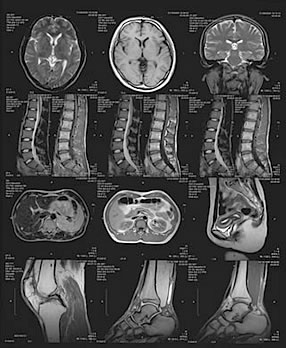

HITACHI ECHELON Smart+(1.5T)

MRI検査とは磁器を利用した検査で、放射線被ばくがなく安全です。当院ではMRI(1.5)を導入し、マルチスライスCTとの検査目的や検査部位などにより使い分け、質の高い診断が可能になりました。

当院では技術とアプリケーションにより、高画質でありながら検査時間を短縮することができました。検査内容によっては最大50%検査時間を短縮でき、従来の1.5T MRIと比較して撮像音を低減しています。

HITACHI ECHELON Smart(1.5T)